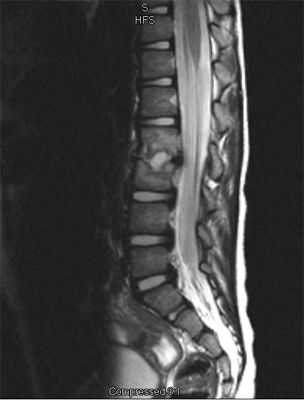

An MRI may be required if further examination of the spine is needed. An MRI machine uses magnetic waves, not X-rays, to show the soft tissues of the body. These tissues include the spinal cord, nerves, and discs. It can also evaluate spinal bones. An MRI allows your healthcare professional to look at slices of the area in question. The test may require the use of dye in an IV. Sedation or anesthesia may be needed to help your child lie still for this test.

A computed tomography (CT) scan may also be ordered. This test is best for evaluating problems with the vertebral bones. Children usually tolerate this test well, however, this test exposes them to radiation, which is significantly higher than during plain x-rays. Sometimes this test may require dye in the spinal canal fluid for easier identification of the spinal cord and nerve root anatomy. When dye is injected for this purpose, the technique is called a myelogram.

In the early stage of the injury an X-ray may not show a fracture. Special imaging tests such as magnetic resonance imaging (MRI), computed tomography scans (CT), or a bone scan may show signs of a stress fracture. Spondylolysis may cause pain in a particular spot in the low back and spasm of the muscles along the spine. Often it will cause pain into the buttocks or thighs. Spondylolysis will often heal with the appropriate rest, a change in activity levels, and by avoiding hyperextension and rotation of the spine. Bracing may be helpful if symptoms do not get better.